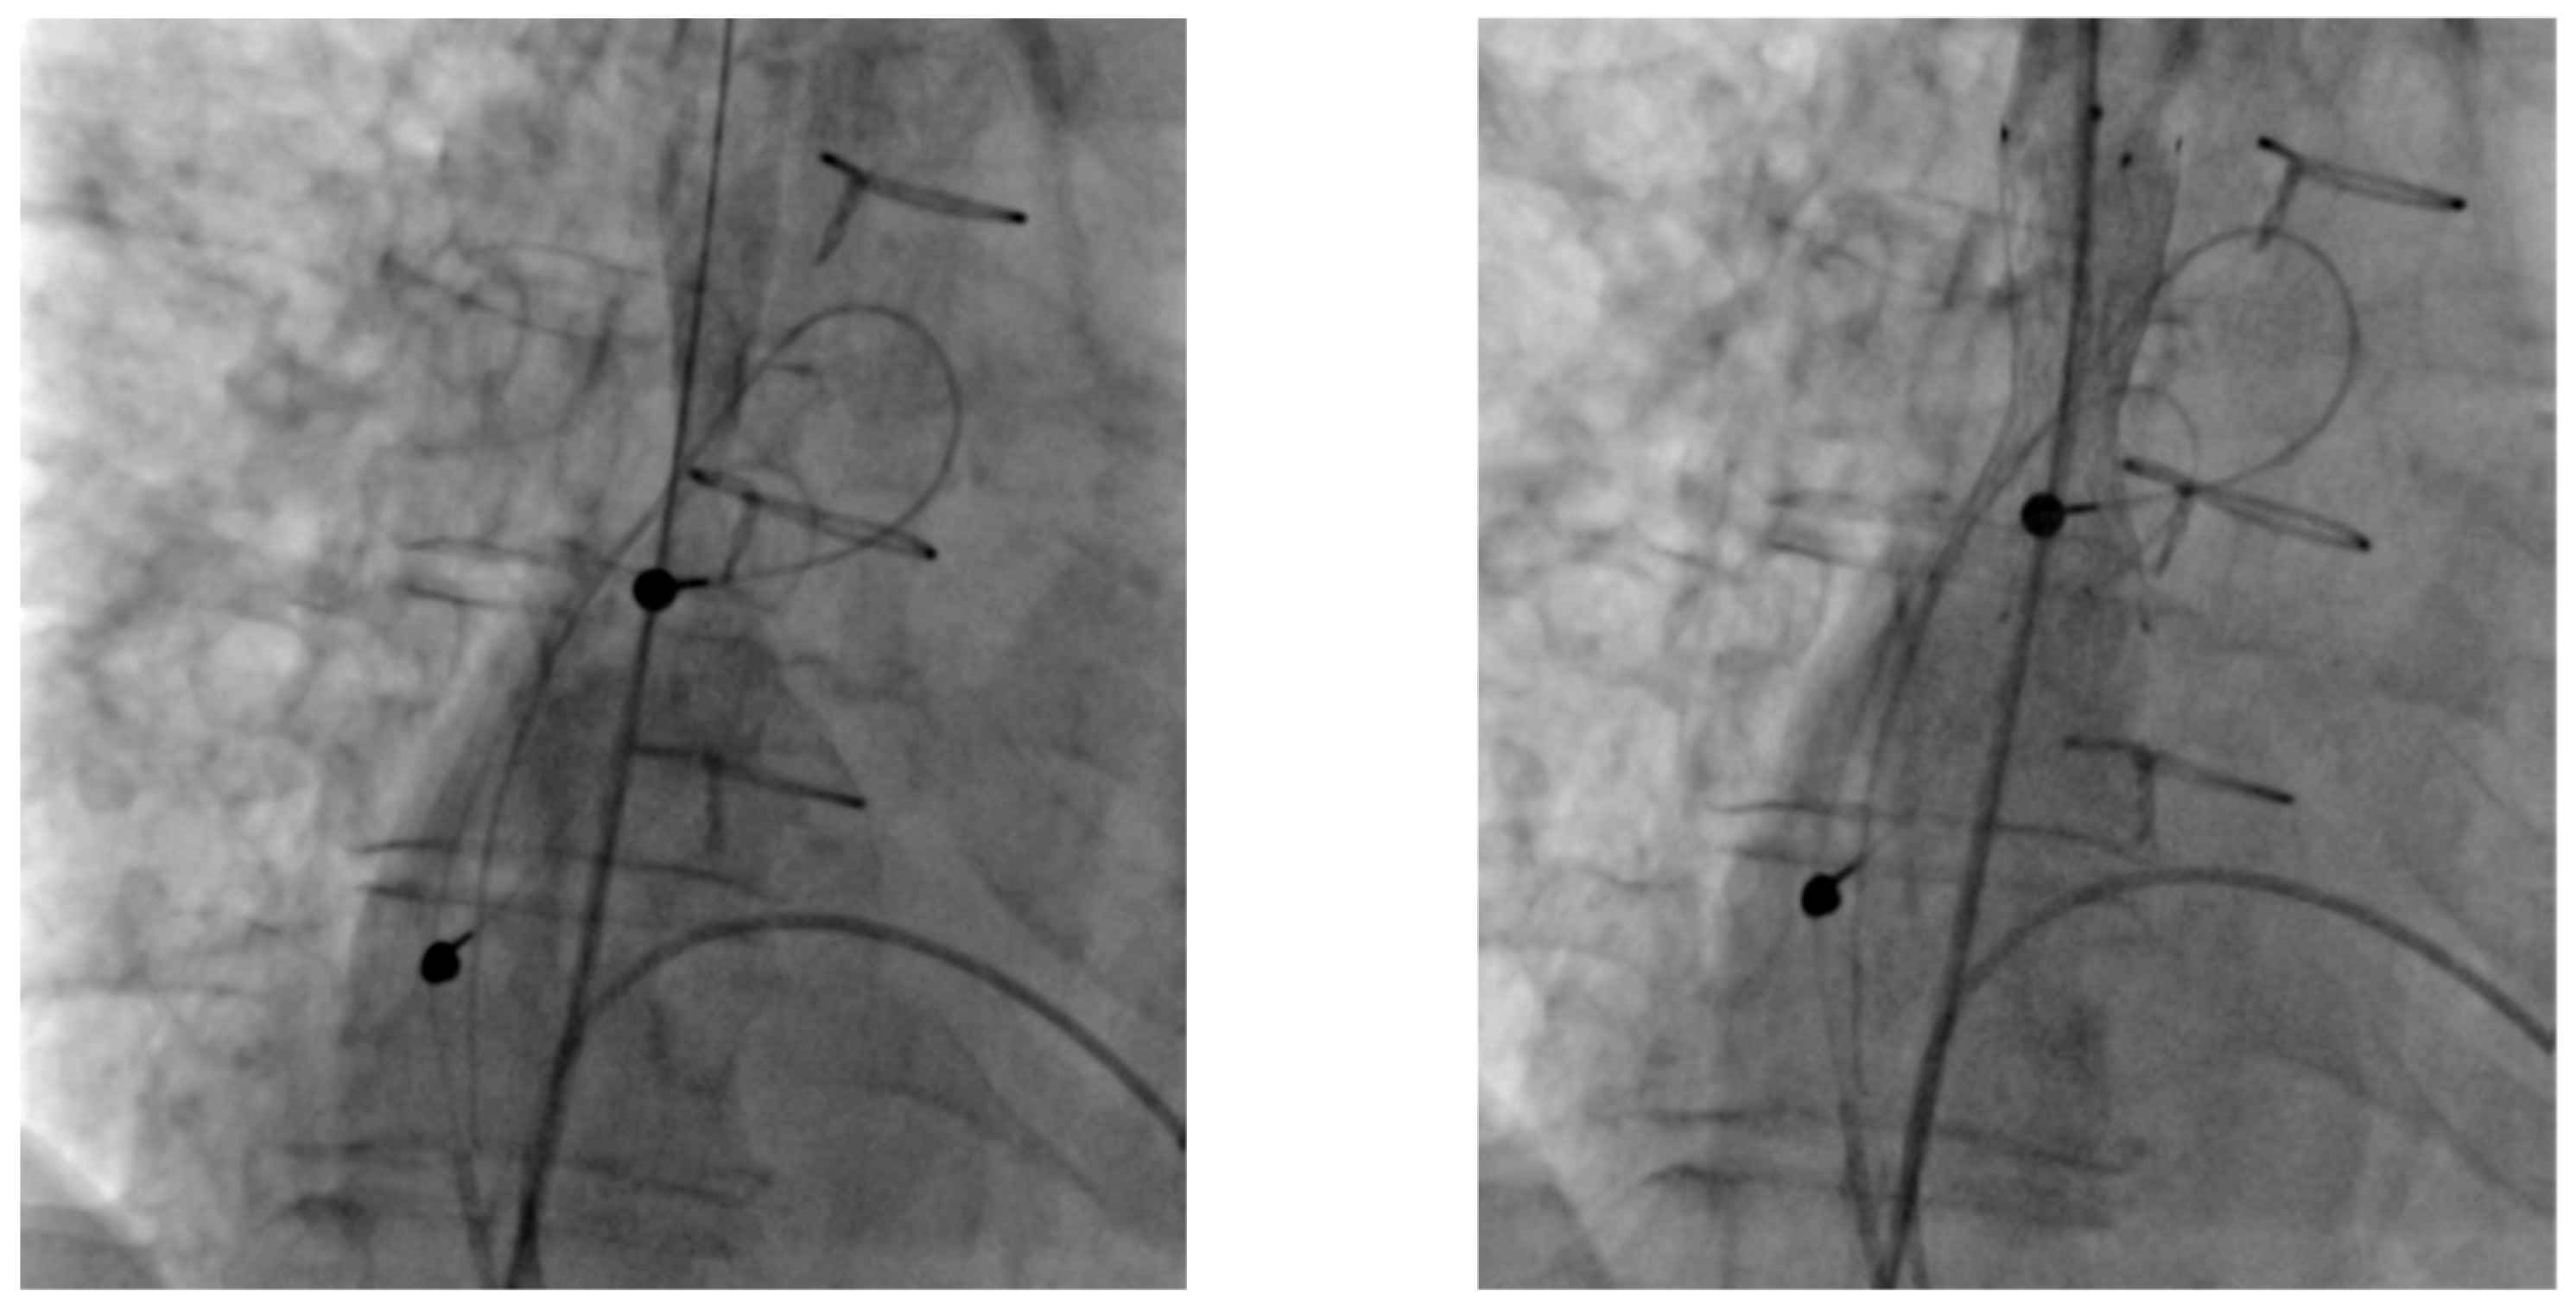

| 9 | 2-chamber pacemaker → CRT-D upgrade | LVEF deterioration, increased ventricular pacing | Left subclavian vein occlusion | Recanalization and PTA via left subclavian vein | Recanalization successful; CRT-D upgrade not possible due to coronary sinus anatomy—upgraded to LBB stimulation system |